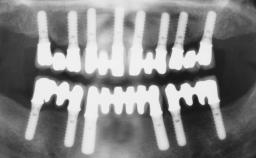

Immediate Loading of Six Implants in the Maxilla and Final Restoration with a Full-Arch Gold/Ceramic FDP Involving the Concept of Tilted Implants

A 61-year-old male patient with a failing fixed maxillary rehabilitation and a fixed mandibular rehabilitation requested a new fixed maxillary rehabilitation. The patient was wearing a temporary metal-reinforced maxillary bridge inserted two years before the consultation. He reported that his previous dentist did not want to insert a definitive framework because he considered the residual teeth to have a negative prognosis. The patient reported a history of recurrent caries and endodontic complications as the main reason for the previous extractions. The anamnesis was negative for periodontal disease and bruxism. The patient’s chief compliant was the mobility of his maxillary prosthesis, which needed to be re-cemented frequently, and discomfort during chewing.Moreover, the patient was not satisfied with the esthetic appearance of his maxillary teeth, which he found too long. The patient asked for a stable and comfortable fixed maxillary rehabilitation and firmly rejected any removable solution.

# of Implants 6

Type of Implants One-Piece|Reduced-Diameter

Bone Augmentation Horizontal|Simultaneous